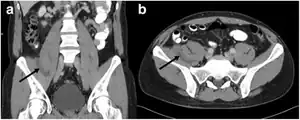

CT scan: right-sided retroperitoneal hibernoma

In general, imaging studies show a well-defined, heterogeneous mass, usually showing a mass which is hypointense to subcutaneous fat on magnetic resonance T1-weight images. Serpentine, thin, low signal bands (septations or vessels) are often seen throughout the tumor.